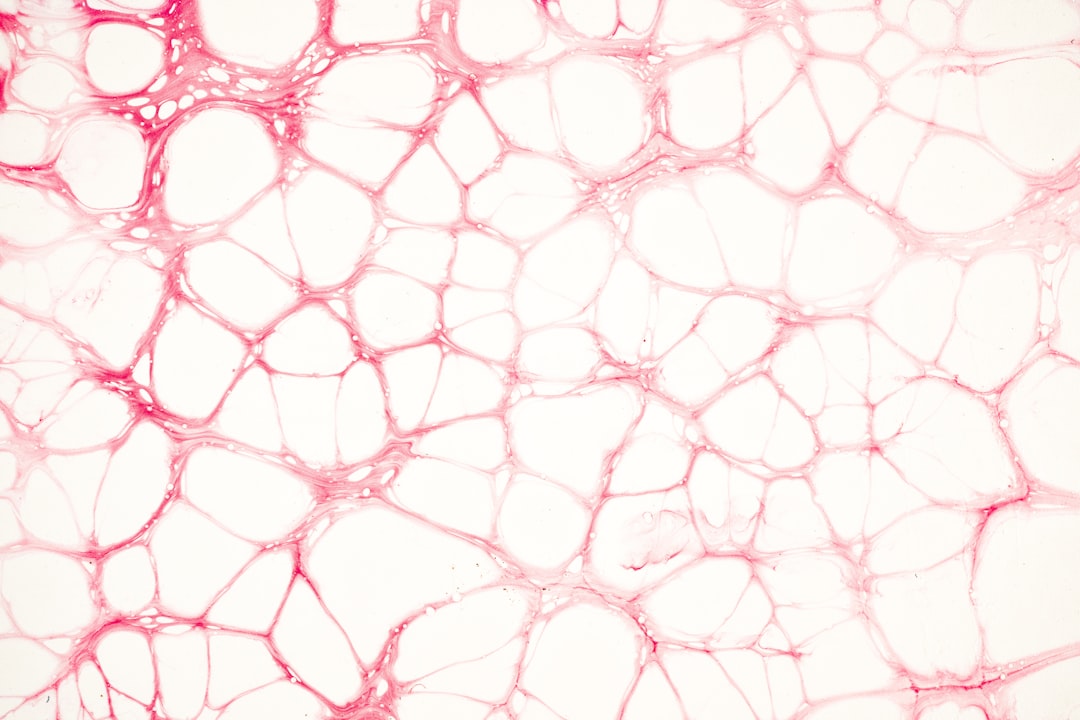

혈관 건강은 전반적인 건강과 직결된다는 사실을 아시나요? 혈관이 건강해야 혈액순환이 원활하게 이루어지고, 이는 곧 우리 몸의 각 기관이 잘 기능할 수 있게 돕습니다. 혈관을 깨끗하게 유지하는 음식과 나쁜 음식 비교를 통해 자신의 식습관을 돌아보는 것이 중요합니다.

특히 최근에는 심혈관 질환이 증가하면서, 혈액 순환의 중요성이 더 강조되고 있습니다. 혈관이 막히면 다양한 질병의 원인이 되며, 이에 따른 예방이 필수입니다. 그러니 우리가 먹는 음식이 얼마나 중요한지 인식하는 것이 필요합니다.